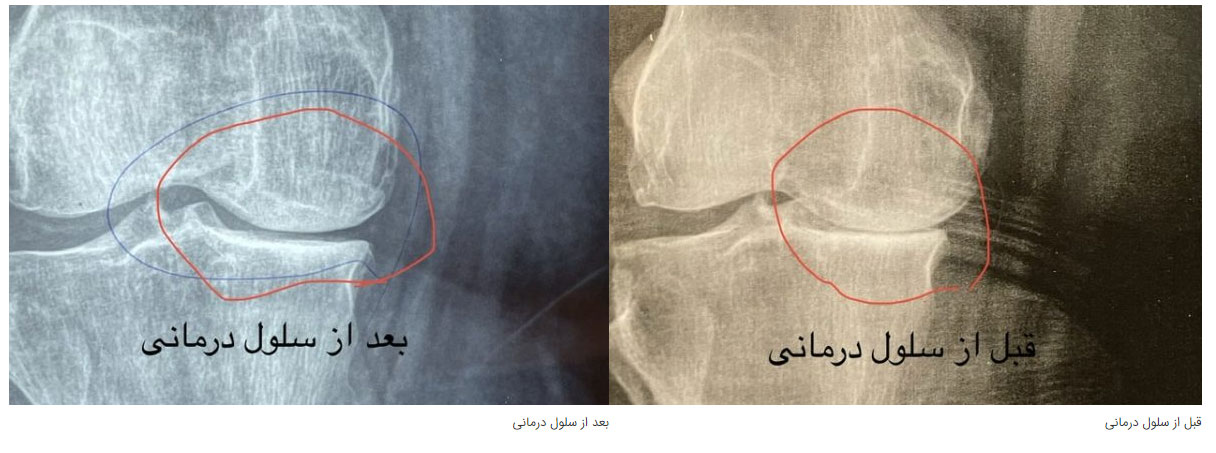

تکنولوژیهای درمانی نوینی مانند سلولدرمانی با بهرهگیری از سلولهای بنیادی، چشماندازهای جدیدی برای بازسازی آسیبهای مفصل زانو به وجود آوردهاند.

در این روش، سلولهای بنیادی، که از منابعی چون مغز استخوان یا بافت چربی بیمار استخراج شدهاند، جدا و تکثیر میشوند. سپس این سلولها به داخل مفصل زانو تزریق میشوند.

این سلولهای بنیادی دارای توانایی ترمیم بافتهای آسیبدیده مفصل، از جمله غضروف، رباط و منیسک هستند. علاوه بر این، آنها به کاهش التهاب، احیای سلولهای مفصلی، و در نهایت بهبود عملکرد مفصل منجر میشوند.

مطالعات نشان دادهاند که سلولدرمانی میتواند به بهبود درد مفصل، افزایش دامنه حرکتی، و بهبود کیفیت زندگی بیماران مبتلا به آرتریت و آسیبهای مفصل زانو کمک موثری نماید.

ولی جدیدترین روشی که امروزه در تمام دنیا برای درمان ارتروز و ساییدگی زانو و ستون فقرات استفاده میشود تزریق مستقیم سلولهای بنیادی داخل زانو یا ستون فقرات یا همان سلول درمانی است . مزیت سلول درمانی نسبت به روشهای پیشین از جمله تزریق ازن یا پی آر پی اینست که این روشها بیشتر برای مفصل حالت تسکین ایجاد میکنند و در واقع مسکن هستند در حالیکه سلول درمانی منجر به تشکیل غضروف در مفصل شده و از طریق ایجاد غضروف درد را از بین میبرد .